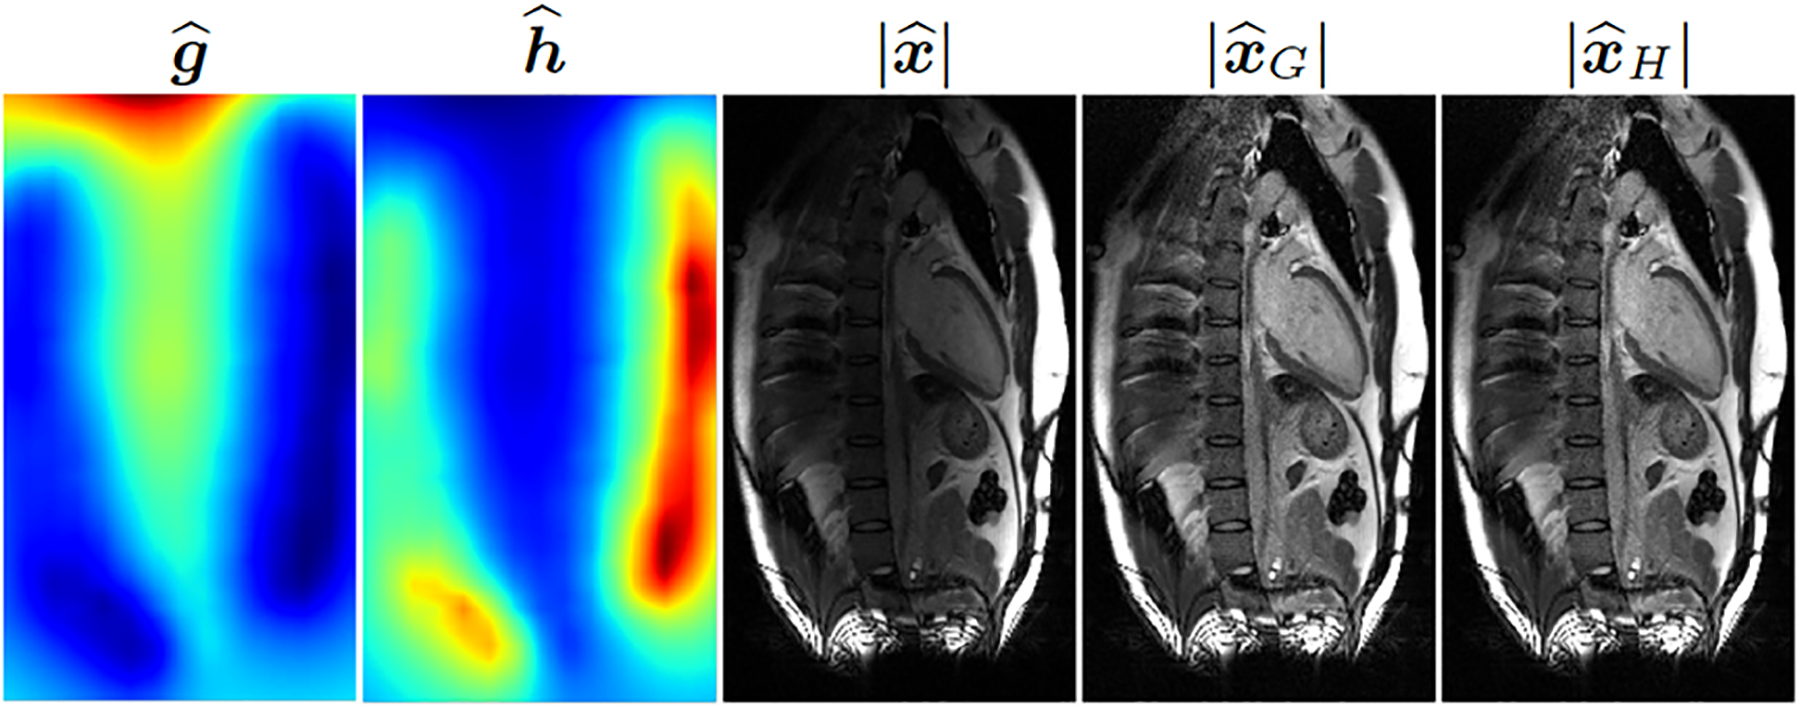

For measured MRI data, single-shot free-breathing T1-weighted images were collected from a healthy volunteer on a 3T scanner (MAGNETOM Vida, Siemens Healthcare, Erlangen, Germany) running on an XA31A platform. The data were collected without contrast using phase-sensitive inversion recovery sequence [7] and were prospectively undersampled at the acceleration rate of two. The raw data file, containing the pre-scan as well as the k-space measurements , was copied from the scanner for offline processing in Python. Representative results are shown in Fig. 4. Both and offer an improvement over the uncorrected image .

Fig. 4:

From left to right, two correction maps and , the magnitude of the uncorrected image, and the magnitudes of the two corrected images. A representative two-chamber view of the heart is shown.